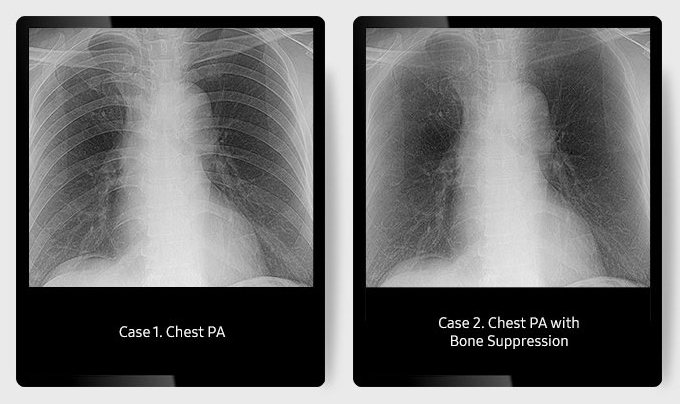

Функция подавления костных тканей Bone Suppression (Опционально)

Функция подавления костных тканей улучшает ясность мягких тканей, подавляя появление костей на грудных изображениях без дополнительной настройки или экспозиции. Она помогает выявлять узлы для точной диагностики.